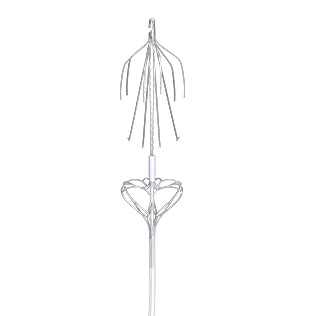

产品介绍

Vewatch®/海神盾™腔静脉滤器通过经股静脉或经颈静脉入路经皮置入,用于预防下腔静脉系统栓子脱落而引起的肺动脉栓塞(PE)。包括:1.已经发生PE或下腔静脉及髂、股、腘静脉血栓形成的患者有下述情况之一者:(1)存在抗凝治疗禁忌证者;(2)抗凝治疗过程中发生出血等并发症;(3)充分的抗凝治疗后仍复发PE和各种原因不能达到充分抗凝者。2.PE,同时存在下肢深静脉血栓形成者。3.髂、股静脉或下腔静脉内有游离漂浮血栓或大量血栓。4.诊断为易栓症且反复发生PE者。5.急性下肢深静脉血栓形成,欲行经导管溶栓和血栓清除者。